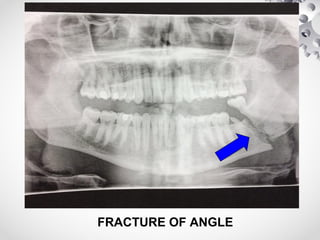

FRACTURE OF ANGLE

CLINICAL FEATURES

• # of Angle, Body & Symphysis

(1) Pain & paradoxical movement; crepitus on distraction of #

segments

(2) Blood stained saliva

(3) Anaesthesia of lower lip

(4) Step deformity palpable externally or intraorally

(5) Asymmetry of lower dental arch & malocclusion

(6) Hematoma in floor of mouth / buccal sulcus